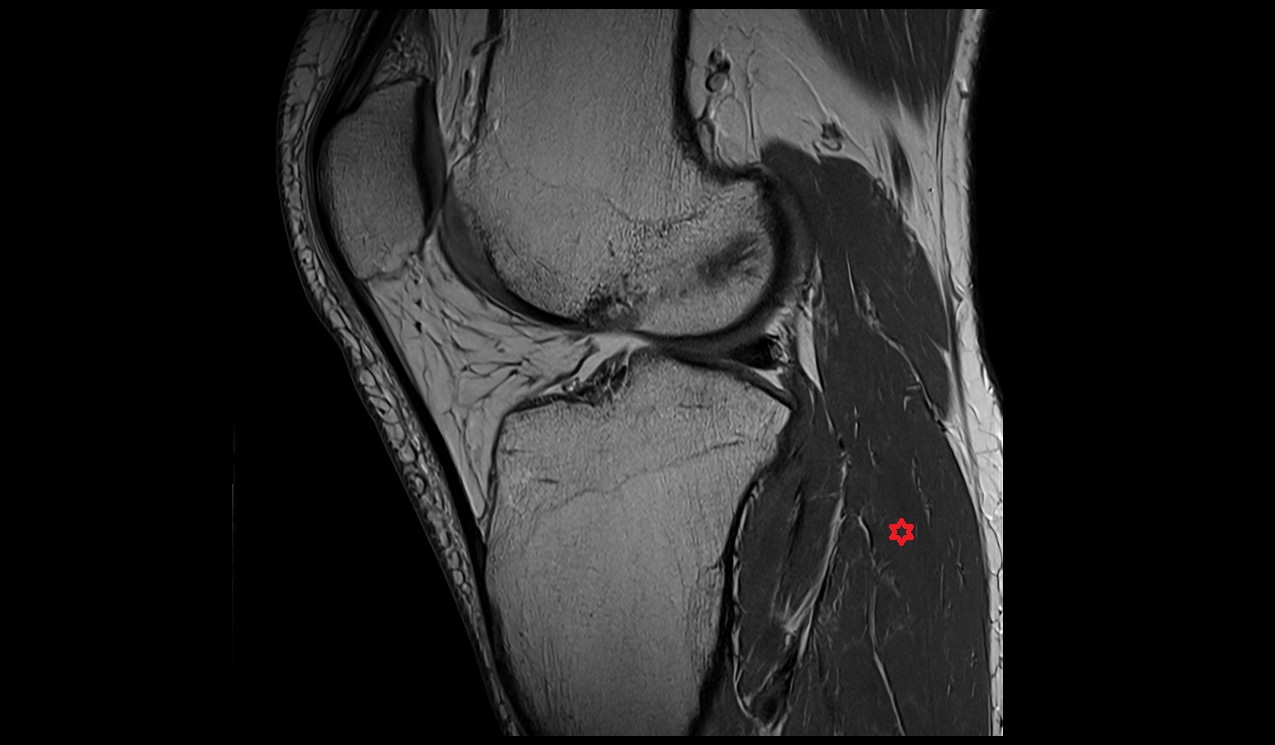

- Anterior cruciate ligament

- Posterior cruciate ligament

- Knee Joint